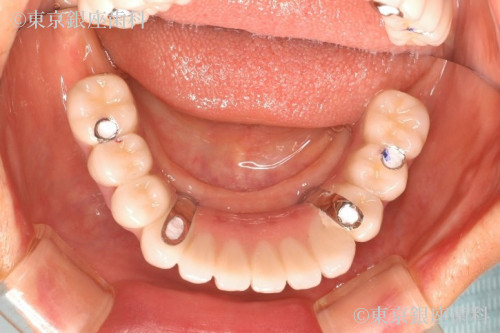

歯周病とむし歯によって咬合崩壊 上下ワンデイインプラントにて再構築した症例

歯周病の進行で歯に動揺があり長期の保存が難しく、臼歯の欠損で咬み合わせが下がって前歯部への負担が大きくなっているため全顎的な治療が必要と判断。最小限のインプラント埋入によって咬合を回復させるため上下ワンデイインプラント処置を計画。

ワンデイインプラント治療で審美性、機能、噛み合わせの高さを同時に解決。また歯周病の影響なのか、OPE前は常に赤ら顔で両ほほに炎症が見受けられたがOPE後改善。術後、歯牙の形態や発音等に不具合を訴えていたが最終補綴物装着時には改善。現在半年メンテナンス。特に問題なし。